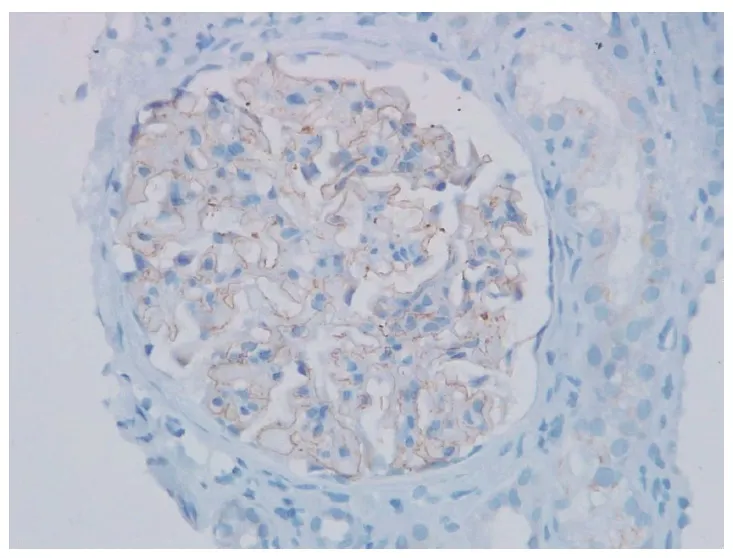

A biópsia renal foi compatível com nefropatia membranosa, além disso, foi identificado marcação na membrana basal glomerular para NELL1 (imuno-histoquímica para NELL1, 400×).

2. A glomerulonefrite membranosa NELL1-positiva é classicamente associada à exposição a mercúrio, mas também pode ocorrer, embora raramente, por intoxicação por chumbo.